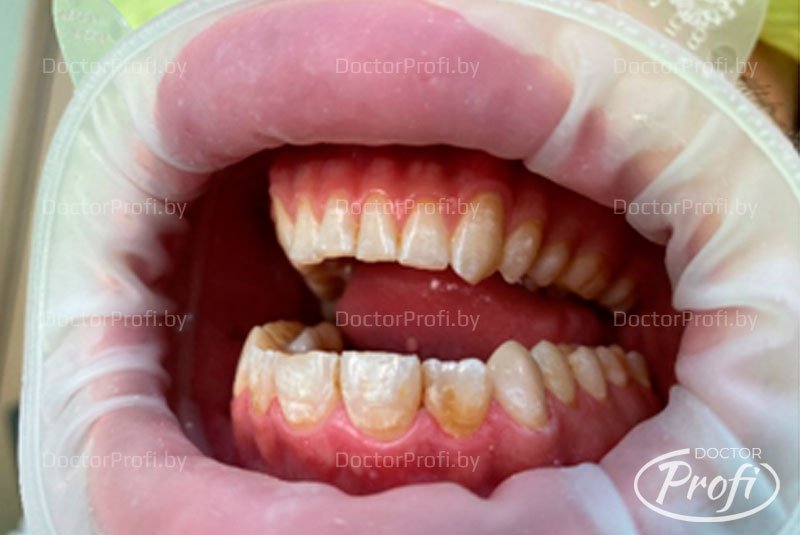

Конфигурация лица не изменена, состояние кожных покровов, красной каймы губ- без видимых патологических изменений. Регионарные лимфоузлы не увеличены, подвижны, безболезненны при пальпации. Движения в ВНЧС в полном объеме, безболезненны. Прикус нейтральный. КПУ=14. OHI-S=1,5(уд.), GI=1,0 (легк.ст).

На вестибулярных поверхностях 12, 11, 21, 22 отмечается наличие белых и пигментированных пятен с нечеткими контурами, слегка шероховатой поверхностью.

Целостность эмали 12, 22 не нарушена, в 11, 21 наблюдаются дефекты эмали в пределах эмалево-дентинной границы. Зондирование пятен безболезненно, термопроба положительна (кратковременная болевая реакция на холод), отмечаются сколы режущих краев зубов 12, 11, 21, 23 в пределах эмали.

Также выявлено сошлифовывание твердых тканей рвущих бугров 13, 23, 33, 43 с формированием площадок стираемости, нарушение клыкового ведения справа и слева.